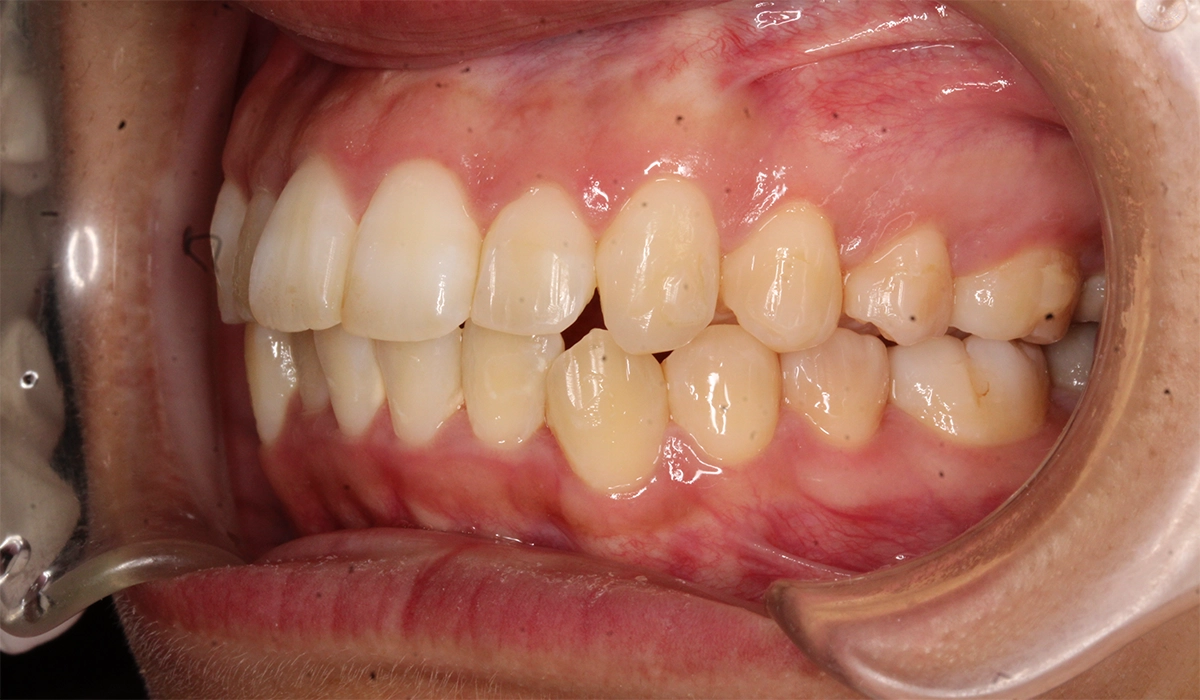

術前:右側

術後:右側